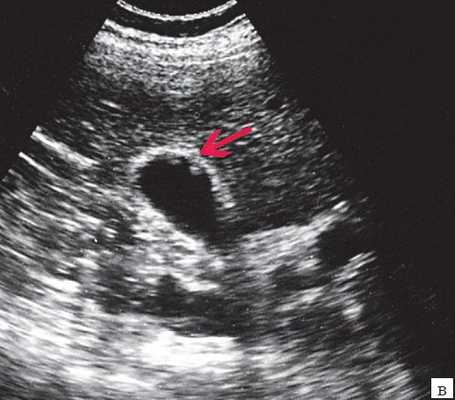

(Левый) Пример неполного кальциноза: у женщины 67 лет, жалующейся на боли в правом верхнем квадранте живота после еды определяются отдельные гиперэхогенные очаги передней и задней стенок желчного пузыря, отбрасывающие неоднородную тень.

(Правый) Пример неполного кальциноза: у мужчины 61 года в стенке желчного пузыря визуализируются точечные кальцинаты. Выявленные при патологоанатомическом исследовании конкременты не визуализируются.